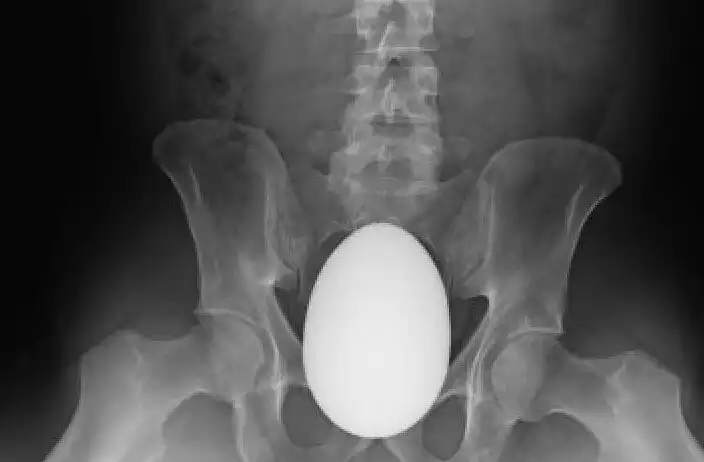

Может, была Пасха?